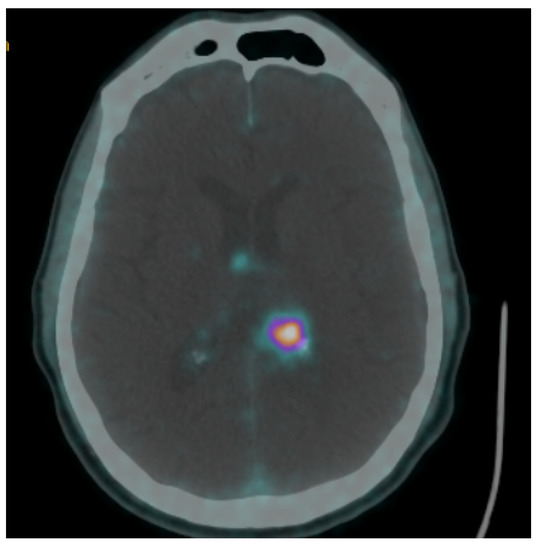

| Assadi, 2021 [61] | Assess radionuclide response | 1/ 1 | Meningioma/ DOTATOC | N/A/ Pre 11.76 Post 9.02 | Reduced SUVmax after radionuclide |

| Barone, 2021 [62] | Assess SUV changes after radiosurgery | 20/ 20 | Meningioma/ DOTATOC | N/A/ Pre 20.8 (2.3–52) Post 12.5 (2.3–44) | Post-radiosurgery reduction of SUVmax in 7/12 patients |